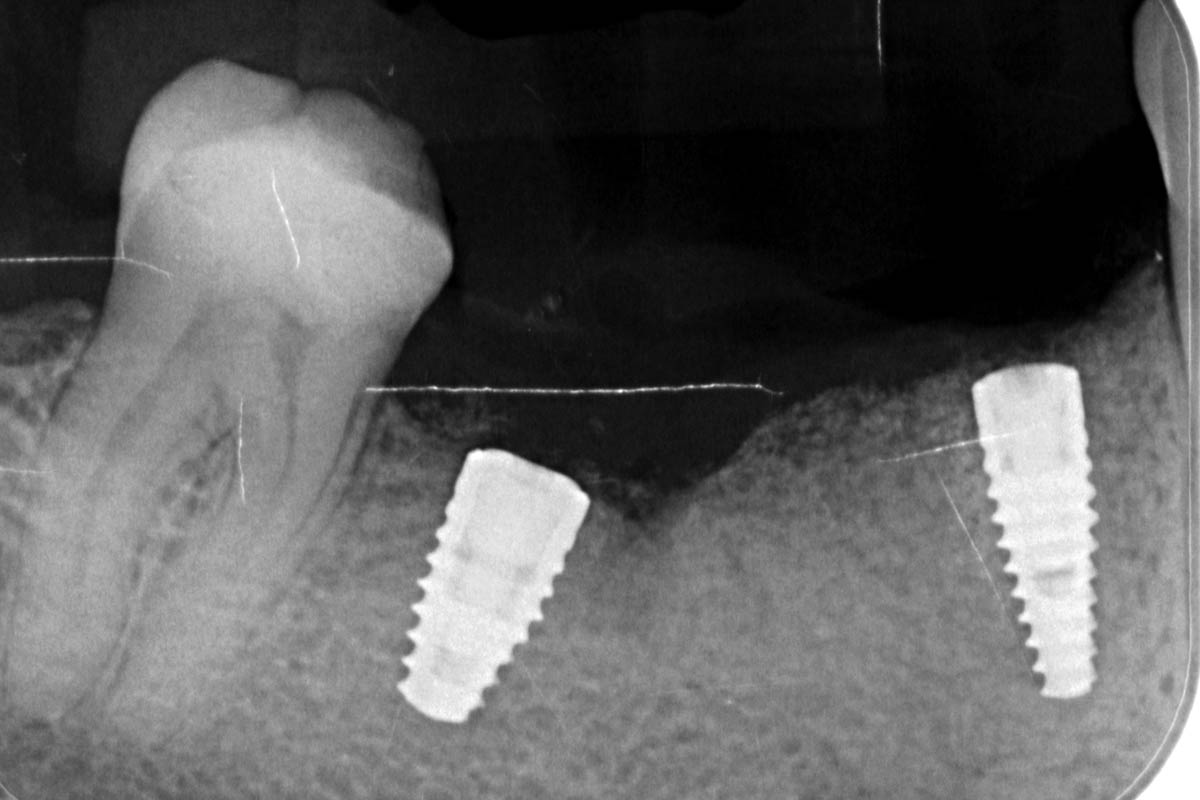

18/29 - Insertion of 2 Straumann BLT implants (regio 4.4: 3.3 x 10 mm, regio 4.6: 4.1x 8 mm), excellent primary stabilityVertical bone augmentation and broadening of attached gingiva using cerabone®, permamem® and mucoderm® - Dr. R. Naimoli

20/29 - X-ray controlVertical bone augmentation and broadening of attached gingiva using cerabone®, permamem® and mucoderm® - Dr. R. Naimoli